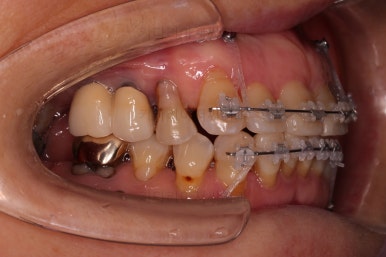

잇몸이 워낙 약하시다보니 힘을 가하는 방향대로 움직이기도 했지만 과반응이 나타나기도 하고 원치 않는 부분에 새로 틈새가 생기기도 했어요.

치료 난이도로 보면 극상의 케이스였어요.

앞니가 약하다보니 앞니들이 통째로 앞으로 튀어나가는 바람에 또 다른 여러 가지 장치를 활용해 주기로 했습니다.